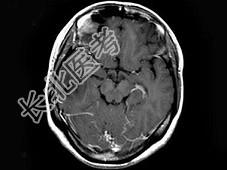

- 单项选择题女,25岁, 头痛3个月,头颅MRI平扫及增强扫描如图, 最可能的诊断是 ( )